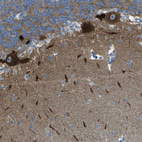

Immunohistochemical staining of human cerebellum shows strong cytoplasmic positivity in Purkinje cells.